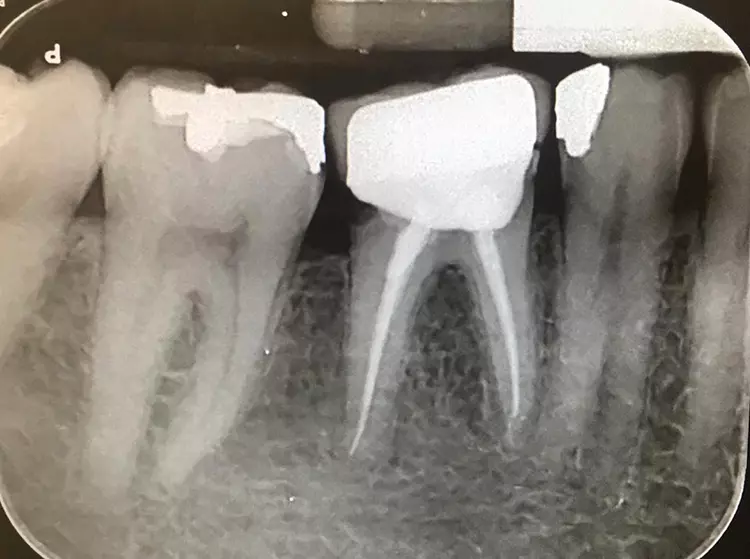

Die klinische Untersuchung zeigte eine klobige Metallkeramikkrone auf Zahn 46. Der Parodontale Screening Index ergab einen Wert von 3 im unteren rechten Sextanten.

Beim Sondieren traten Blutungen auf, die distal von Zahn 46 stärker ausgeprägt waren. Daher wurde an dieser Stelle ein weiteres 6-Punkt-Taschendiagramm erstellt, das Taschen von 4 mm Tiefe auf der distobukkalen Seite von Zahn 46 mit Blutungen zeigte. Zusätzliche Perkussionstests im unteren rechten Quadranten ließen erkennen, dass Zahn 46 nicht auf Perkussion reagierte.

Im vorliegenden Fall ging es um die Behandlung einer Karies an einem Kronenrand. Nach Entfernung der Krone und der Karies wurde zum Wiederaufbau des Zahnstumpfes das thermoviskose Komposit VisCalor bulk (VOCO) verwendet. Um eine ausreichende Materialstärke des Abformsilikons an den Rändern zu gewährleisten und um dadurch ein Einreißen oder Verziehen beim Entfernen zu verhindern, ist eine Sulkusbreite von 0,2 mm zwingend erforderlich [7].